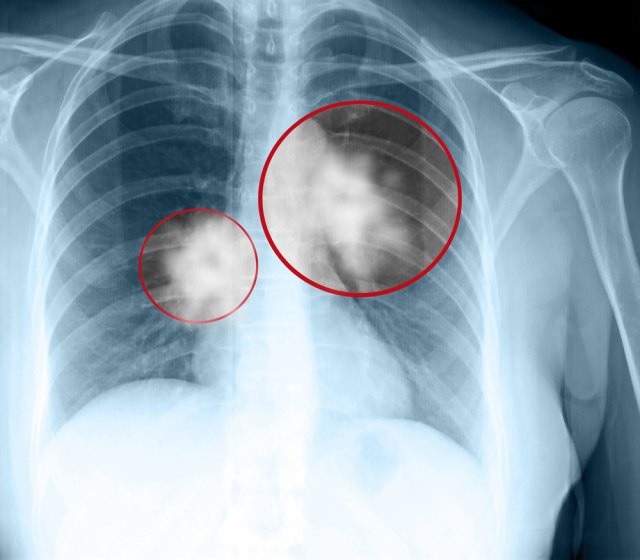

Zašto mnogi nepušači dobiju kancer pluća?

Rak pluća je jedna od najčešćih i najtežih vrsta kancera. Prema podacima Američkog društva za rak, procenjuje se da će u ovoj godini biti 235.760 novih slučajeva raka pluća.

"Rano otkrivanje bolesti jedini je način da se rak pluća leči. Svi terapijski postupci po pravilu mogu produžiti život za koju godinu, a nove ciljane terapije 4 do 5 godina. Ali, ne nude izlečenje. Izlečenje od karcinoma pluća moguće je isključivo ranom dijagnostikom i ranim operativnim zahvatom", rekao je ranije medijima hrvatski akademik Miroslav Samaržija.